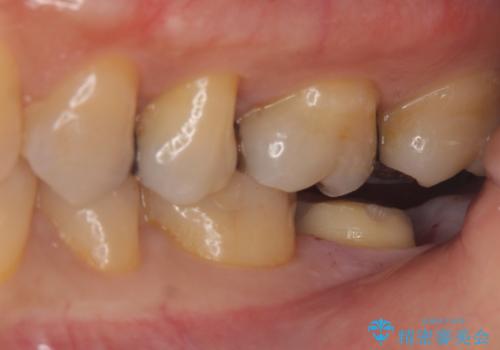

銀の詰め物が取れた。

- 銀の詰め物が取れたとのことで来院。

詰め物の下には虫歯がありました。

白い物で治療して欲しいとのことで、セラミックの詰め物だと詰め物の範囲が大きく、割れてしまう可能性があるので

ジルコニアクラウン(被せもの)で治療を行いました。

銀の詰め物はかなり昔に治療されたそうです。

銀の詰め物は虫歯の再発リスクが高く、歯に痛みが出てしまうと歯の神経の治療もしないとならなくなってしまいます。